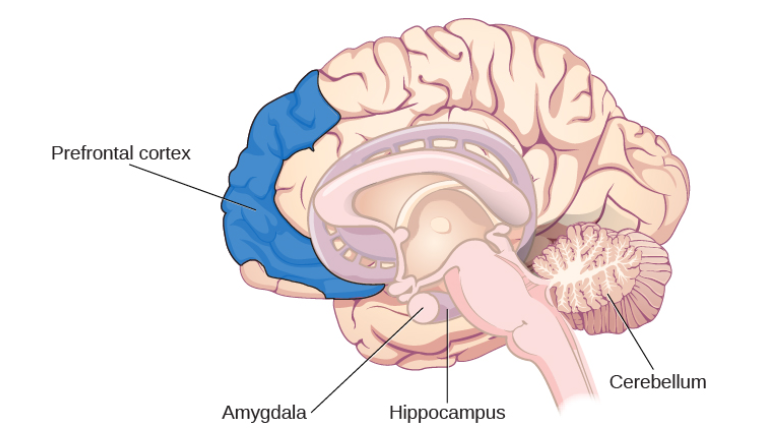

Many researchers believe that the entire brain is involved with memory, in some way or another (Lashley, 1950). However, some key areas have been identified (shown below in Figure 1.) and include the amygdala, hippocampus, cerebellum, the prefrontal cortex and the synapses linking them all (Mayford, Siegelbaum, & Kandel, 2012).

However, as research has developed, and the mapping of the brain and its functions has developed researchers are becoming able to pinpoint the structure’s role within memory, such as the amygdala facilitating the encoding of memories to a more significant degree when the event is emotionally arousing (Josselyn, 2010). This means that when an individual suddenly fails to respond to stimuli that normally would have induced a fear response; a neurologist can narrow down their investigation and begin imaging of the amygdala with the expectation of some sort of abnormality (e.g. a lesion or tumour) affecting it’s functioning.